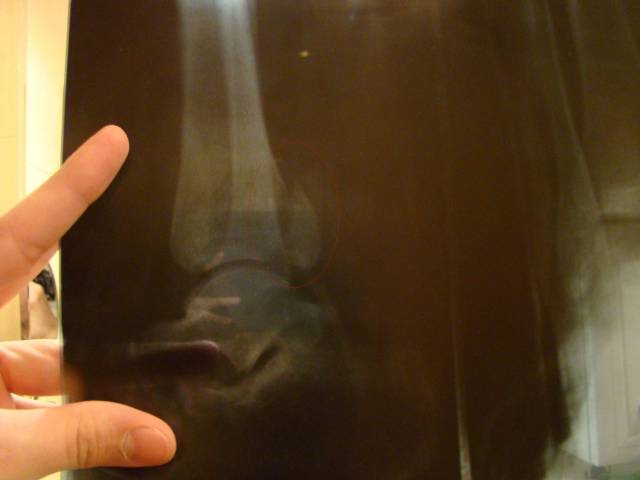

Главная > Железки > Поломки и падения

закрытый перелом заднего края дистального эпифаза большеберцовой кости левой голени со смещением отломка и подвывихом стопы сзади

это фото после операции..упал в адренлине..а лежал в клинеческой больнице управления делами президента